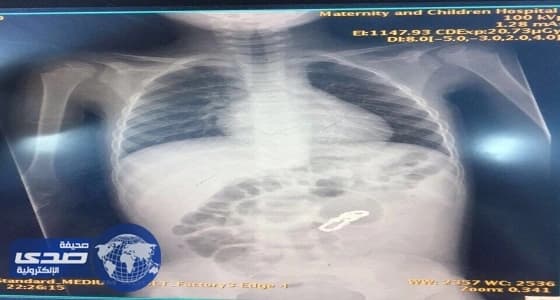

أنقذ فريق طبي بمستشفى الولادة والأطفال بالمساعدية بجدة اليوم، طفل يبلغ من العمر سنة ونصف سنة، حيث أدخل المستشفى عن طريق قسم الطوارئ وكان يعاني من إستفراغ وآلام حادة بالبطن وإمساك منذ أربعة أيام.

وأتضح من خلال الأشعة التي أجريت له في أحد المستشفيات الخاصة سابقاً وجود جسم غريب يشبه القطع المعدنية الشبكية في البطن.

وعلى الفور تم إجراء عملية جراحية استكشافية إثر حالته، واكتشف الفريق الطبي وجود ثقوب في الأمعاء الدقيقة وناصور بين أجزاء الأمعاء المتلاصقة نتيجة بلع القطع المغناطيسية، مما أدى إلى ثقوب في الأمعاء وأجري للطفل قص الأجزاء المثقوبة وتوصيلها ويتمتع الطفل حالياً بحالة صحية مستقرة.